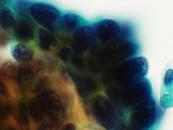

第38回日本臨床細胞学会九州連合会学会(熊本)スライドカンファレンス症例3

種別:消化器・口腔

出題:甲斐 敬太 佐賀大学医学部附属病院病理部

| 年齢 | 60代 | 性別 | 男性 |

|---|---|---|---|

| 採取部位 | 胆汁 | 採取方法 | 経皮経肝胆道ドレナージ |

| 検体処理法 |

臨床所見

既往歴:潰瘍性大腸炎治療中。

現病歴:難治性の十二指腸潰瘍を合併し、通過障害をきたしていた。閉塞性黄疸が出現し、精査で原発性硬化性

胆管炎が疑われた。減黄目的に経皮経肝胆道ドレナージが行われ、胆汁が提出された。なお、狭窄部の

胆管と十二指腸潰瘍部から生検が行われたが、悪性所見は指摘できなかった。

| 正解 | 5.腺癌 |

▼選択肢及び投票結果

| 1.急性胆管炎 (反応性異型) | 1件 | (1.0%) | |

| 2.原発性硬化性胆管炎 (反応性異型) | 25件 | (24.0%) | |

| 3.Low-grade BilIN | 31件 | (29.8%) | |

| 4.Low-grade IPNB | 19件 | (18.3%) | |

| 5.腺癌 | 28件 | (26.9%) | |

| 投票総数 | 104件 | (100%) |